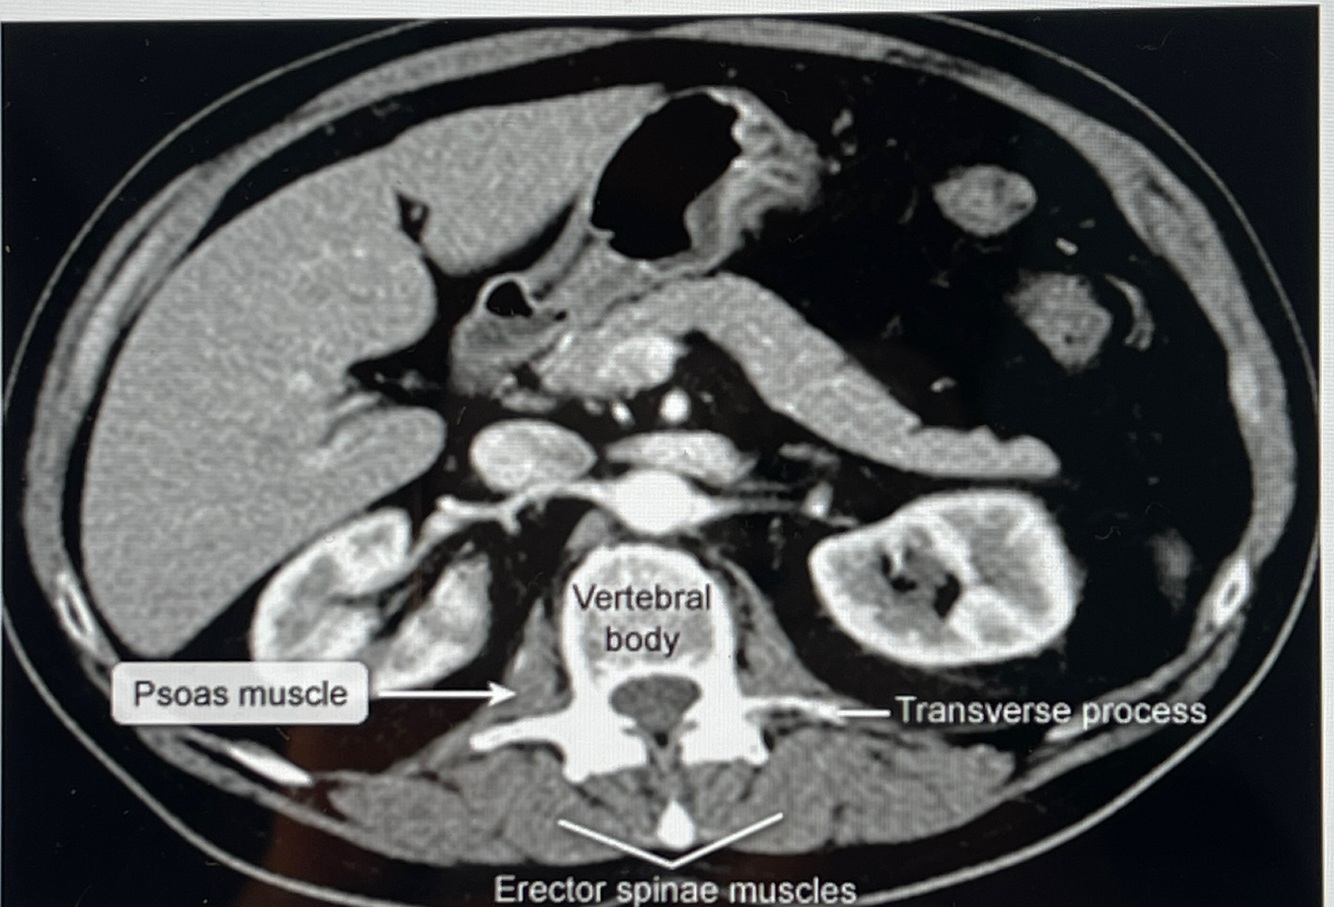

How well did you know this?